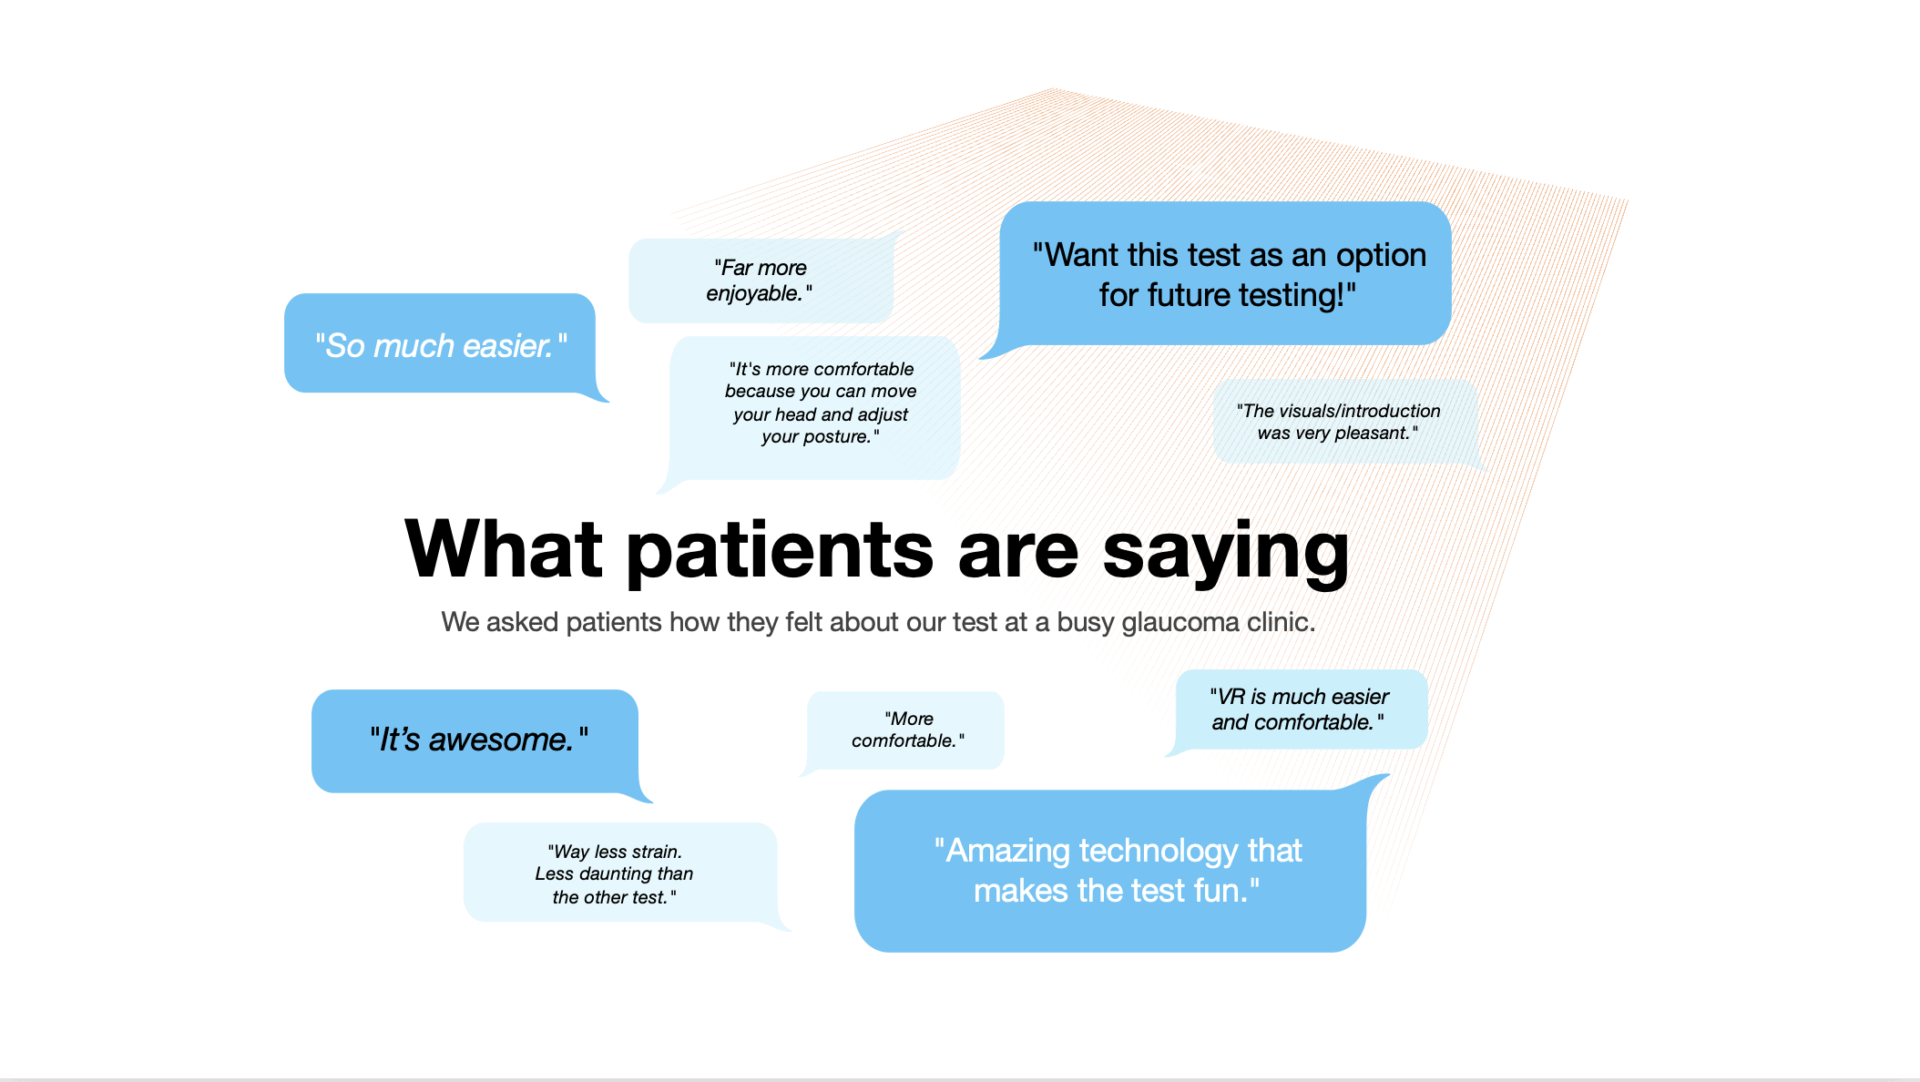

Comparing the Usability of a Portable Virtual Reality Device with the Humphrey Visual Field Machine in Clinical Settings

Examines differences in patient comfort, confidence, and ease of use when completing visual field testing on VR-based versus traditional perimetry systems. (ARVO 2023)

Virtual Reality Perimeters A More Comfortable, Engaging and User-Friendly Alternative

Assesses patient experience across comfort, focus, and engagement to identify how VR-based perimetry can improve accessibility and satisfaction in clinical care. (NANOS 2024)